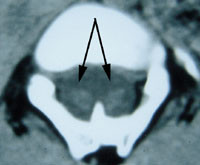

Diastematomyeli

Ved diastematomyeli er ryggmargen spaltet i sagittalplanet, slik at man på ett eller flere nivåer har to separate ryggmarger (1) (fig 6). De to ryggmargene kan ha hver sin durasekk (type 1), og tilstanden skyldes da en beinspore som peker posteriort fra bakre del av corpus på ryggvirvelen og ”spalter” ryggmargen. Alternativt finner man to ryggmarger innenfor samme durasekk (type 2), og et fibrøst drag eller en beinspore skiller ryggmargene (8). Felles for begge typer diastematomyeli er høy risiko for tjoret ryggmarg. Diastematomyeli er ofte ledsaget av en fortykket filum terminale og lumbosakrale hårdusker (1). Hos omkring halvparten finner man også en ledsagende syringomyeli (1).